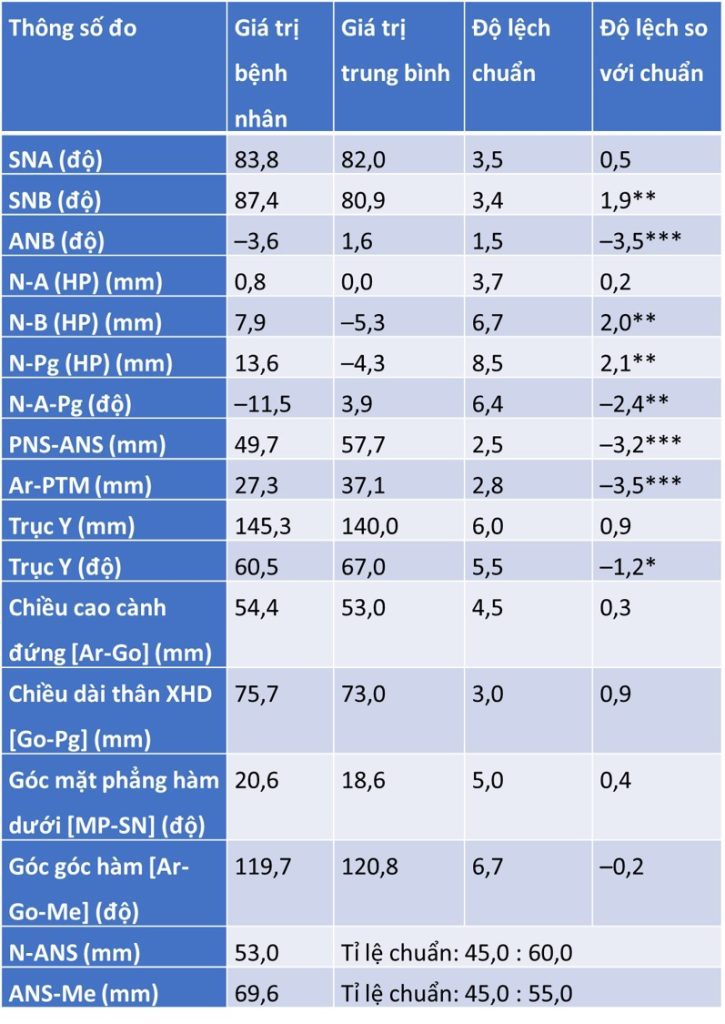

Tóm tắt phim sọ nghiêng (hình 2-16 và bảng 2-11 đến 2-14)

Tương quan xương hạng III với profile xương lõm, bao gồm:

- Xương hàm dưới nhô ra so với nền sọ

- Khớp cắn bù trừ với răng cửa hàm trên nghiêng ra trước và răng cửa hàm dưới nghiêng vào trong

- Chỉ số Wits loại III

- Profile mô mềm lõm

- Môi dưới nhô ra

- IMPA thấp hơn chuẩn 1,2 SD → răng cửa dưới hơi nghiêng vào trong.

- U1–Palatal plane cao hơn chuẩn 1,3 SD → răng cửa trên nghiêng ra trước.

- Góc liên răng cửa cao hơn chuẩn 1,1 SD → khớp cắn bù trừ (răng cửa trên nghiêng ra, răng cửa dưới nghiêng vào).

- Wits âm nhiều (–5,7 mm, lệch 4,7 SD) → đặc trưng của sai khớp cắn hạng III xương.

- Profile mặt lõm, loại xương và mô mềm hạng III.

- Khớp cắn hạng III ở cả răng cối lớn và răng nanh.

- Cắn chéo răng trước với overjet âm 1–2 mm.

- Cắn sâu nhẹ: 10% overbite.

- Hàm trên lệch (cant) với lộ nướu nhẹ bên phải khi cười.

- Cằm lệch 7–8 mm sang trái so với đường giữa mặt.

- Đường giữa răng hàm dưới lệch 1,5 mm sang trái.